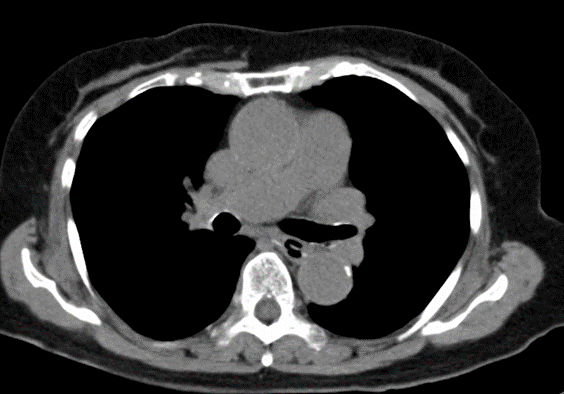

70歳男性。 6か月前から固体や液体を飲み込むのが徐々に困難になり、誤嚥が頻繁に起こるため内科受診となった。 身体所見では、肺野にcoarse crackleを…